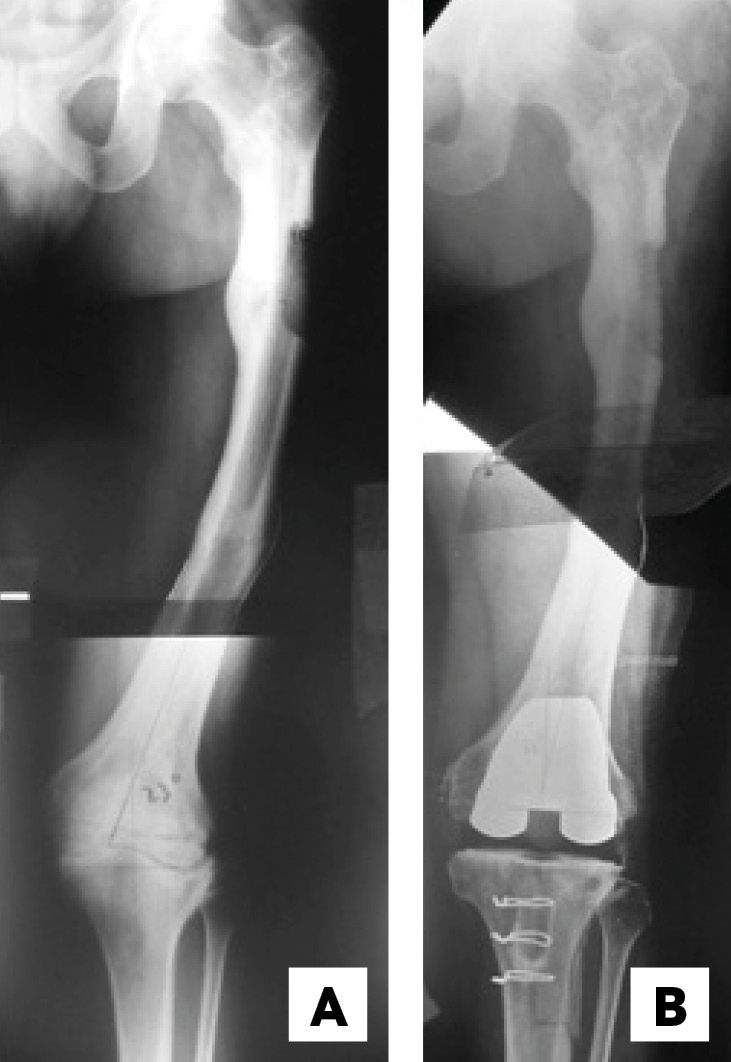

There were 16 varus knees (average intra-articular deformity 9.2°) and 13 valgus knees (average intra-articular deformity 16.6°). The extra-articular deformity was situated in the distal third of the femur in 12 (Figure 1), in the middle third of the femur in 4 patients (Figures 2 & 3), in the proximal third of the tibia in 9 and in the middle third of the tibia in 4 . Regarding the type of deformity, all patients had a coronal deformity, 13 in varus (average 16.3°), 15 in valgus (average 14.4°) and 1 with a medial displacement of the distal femoral epiphysis of 3 cm. (Figure 1). In 8 patients, the deformity was biplanar with alterations in the sagittal plane, 4 in flexion and 4 in extension, with an average of 19.7° and 8° respectively. No patients showed a significant rotational deformity.

In the radiological evaluation it is important that the weight bearing AP view includes the femoral head and the ankle in standing position. If this kind of studies are not available, conventional X-rays may be used, taken separately, with the same magnification to afterwards put together the limb as a puzzle (Figure 2). The knee must be in extension and in neutral rotation. These images will allow to evaluate the effects of the deformity in the final axis of the limb, measure the implant and calculate the necessary bone resections. It is advisable to also have a conventional AP view centred on the joint line.[2], Mullaji Arun, Shetty GM Computer-Assisted Total Knee Arthroplasty for arthritis with extra-articular deformity. J. Arthroplasty. 2009;24(8):1164.[3] Panayiotis JP, Karachaloios T, Themistocleous GS Total knee arthroplasty in patients with pre-existing fracture deformity. Orthopedics. 2007;30(5):373.